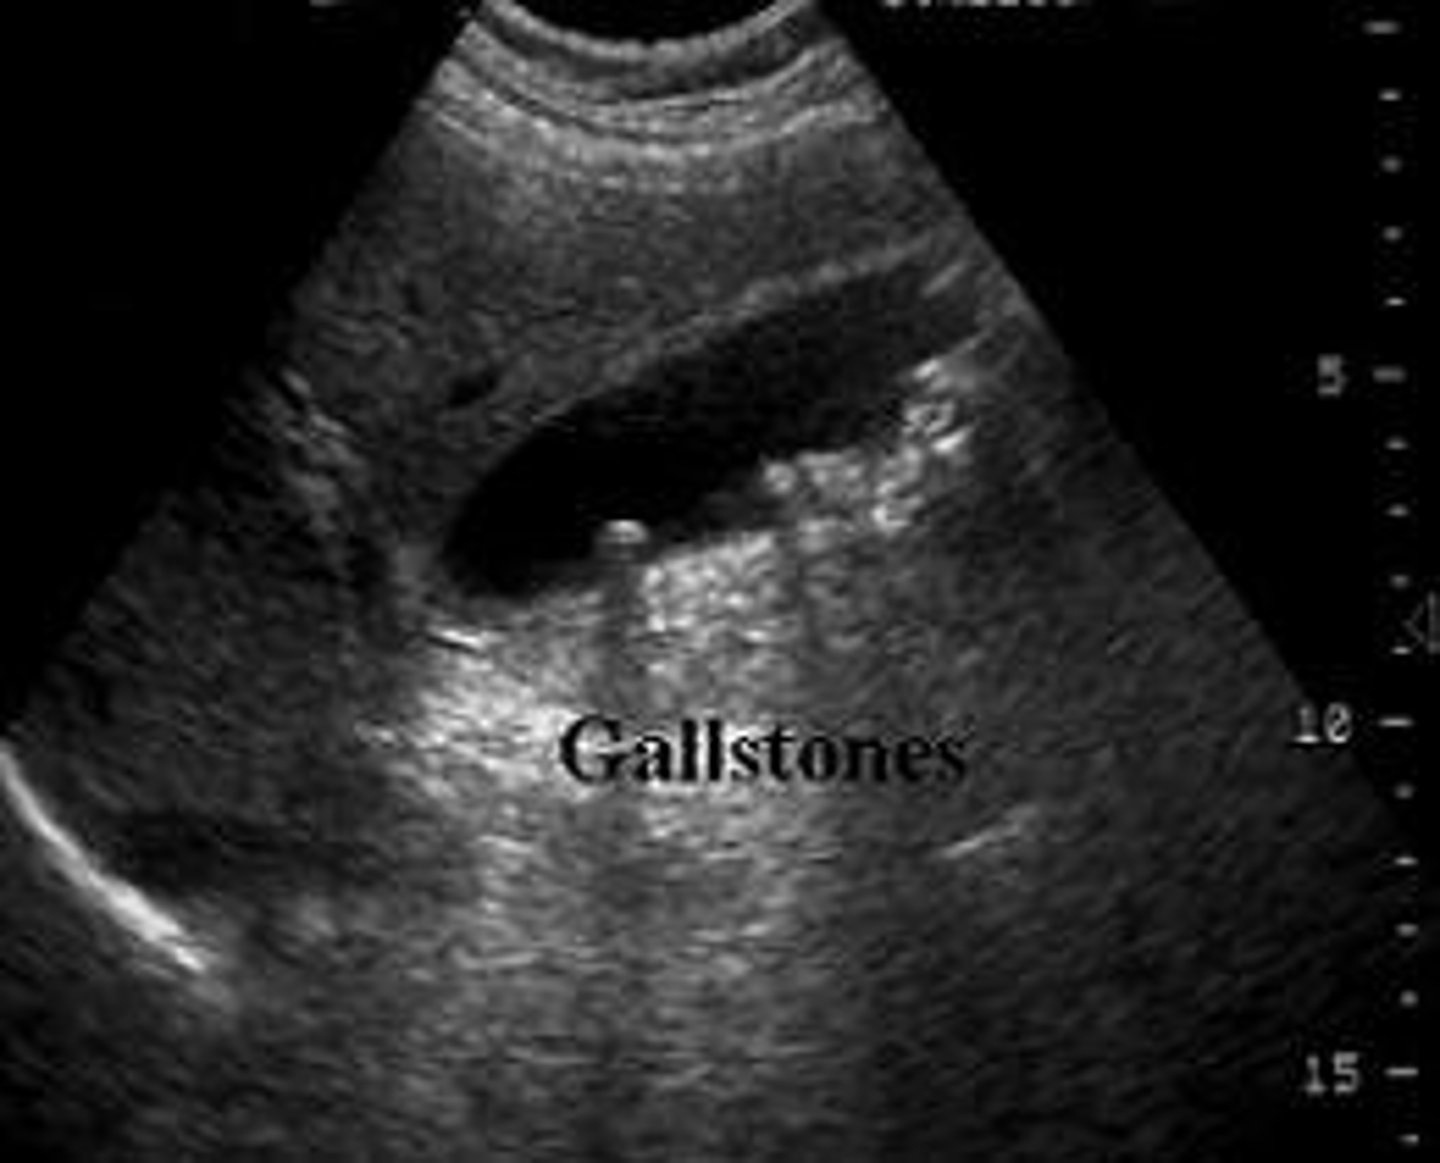

What are diagnostic ultrasounds used for?

View organs & evaluate motion (cardiology, OBGYN, GI, & vascular medicine)

Diagnostic ultrasound

Echoes of the US beam bounce off interfaces between tissues with different acoustic properties

-Sends high-frequency sound into patient & assesses strength & time of returning echoes

-Echoes caused by changes in density

<p>Echoes of the US beam bounce off interfaces between tissues with different acoustic properties</p><p>-Sends high-frequency sound into patient &amp; assesses strength &amp; time of returning echoes</p><p>-Echoes caused by changes in density</p>

What are ultrasounds used for?

Obstetrics, cardiology, vascular, abdominal

US advantages

Inexpensive, non-invasive, no radiation

US limitations

Quality is technician-dependent

-Pt body habitus